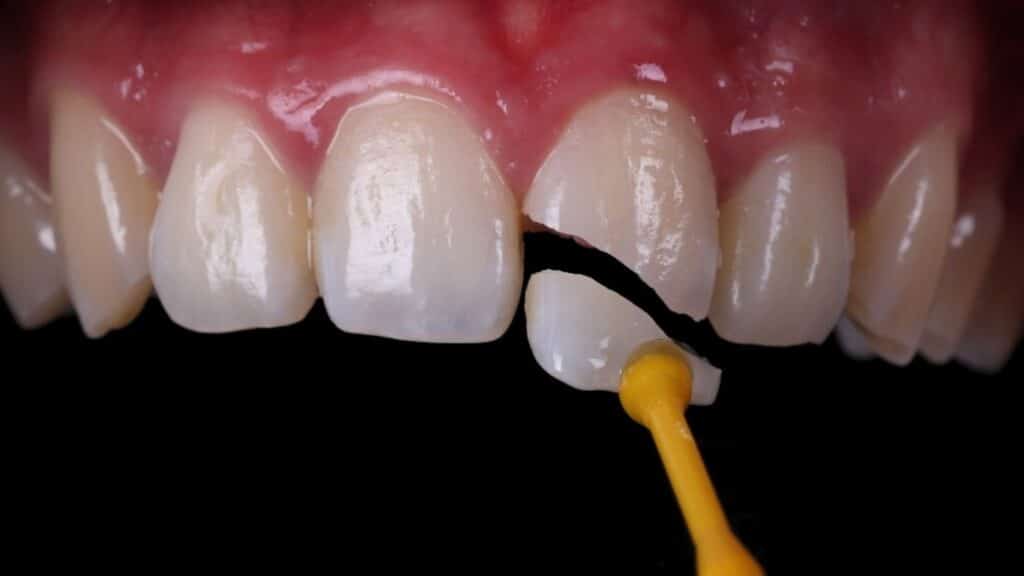

How much does teeth whitening cost in Marbella?

With the arrival of summer, many people are looking to improve their smile so they can feel more confident on holiday, at events, at weddings or simply in their day-to-day lives.